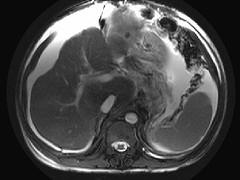

问题 男,44岁,有乙肝病史,现腹胀,右上腹痛,消化不良,消瘦、乏力、贫血、黄疸,血清转氨酶升高,白蛋白/球蛋白比值倒置。CT、MRI检查如下图,最准确的诊断是 ( )

选项 A.肝硬化并腹水 B.肝硬化并腹水、再生结节 C.肝硬化腹水、肝癌 D.肝硬化并再生结节 E.肝硬化并腹水、脂肪肝

答案 B